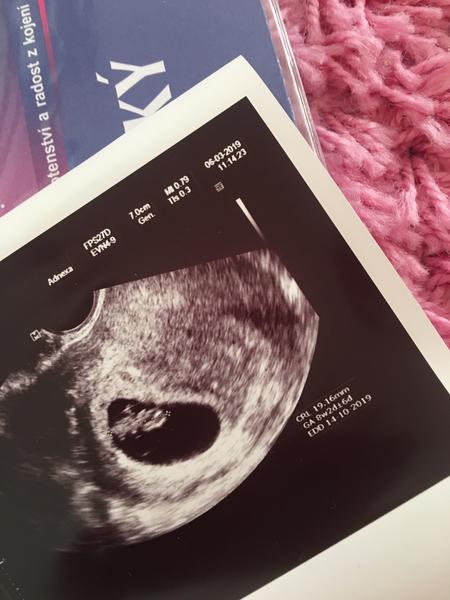

@marcelina14 jdu od dr, jsem 7+2 a slysela jsem srdicko ❤️🥳 spadl mi kamen ze srdce

@marcelina14 juuu krasna fotecka miminka.gratulace největší